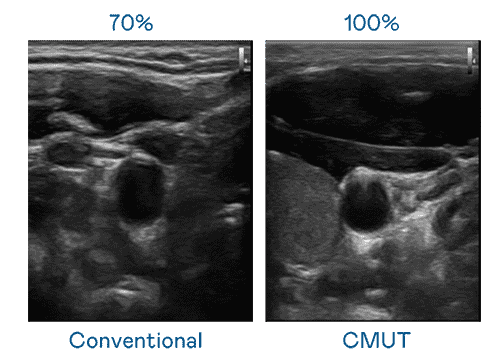

CMUT 技术是一种用电容式微机电元件来产生超音波讯号的技术。。与传统 PZT 压电式技术相比,,,CMUT 频宽增加 30%,,更宽频的超音波讯号让影像解析度大幅提升,,是实现高影像品质医疗超音波扫描、、、促进精准医疗发展的关键技术。。。。

大频宽带来超清晰影像

超音波影像的解析度高低,,首先取决于探头能发出的讯号频宽。。。。尊龙集团 CMUT 可提供高清晰的超音波讯号,,提供高频宽、、高灵敏度、、、影像纹理细节更高的超音波影像,,,,协助医护人员缩短影像判读时间及利用精准的医疗影像进行诊断。。。。